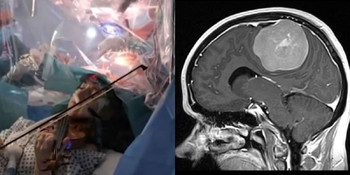

Dia mencipta kejutan apabila dengan selamba menggesek biola semasa sekumpulan doktor sedang berusaha mengeluarkan ketumbuhan di tengkorak kepalanya atau otak.

Wanita berkenaan bernama Dagmar Turner, 53 tahun berbuat demikian supaya doktor pakar yang menjalankan pembedahan itu mampu melihat keupayaannya bermain muzik.

Wanita berkenaan yang juga merupakan bekas perunding pengurusan dari Isle of Weight itu memainkan biola semasa pembedahan bagi mengeluarkan ketumbuhan di bahagian kanan lobus frontal otaknya.

Ia berhampiran dengan bahagian untuk mengawal pergerakan di tangan kirinya.

Bagi mengelakkan Turner hilang upaya untuk bermain biola, Perunding Pakar Neuro di Hopital King’s College, Profesor Keyoumars Ashkan, membuat perancangan dengan melakukan lakaran membuka tengkorak kepala Turner

sambil dia menggesek alat muzik itu semasa pembedahan dijalankan.

” Semasa doktor melakukan pembedahan di bahagian otaknya, Turner bermain muzik Gustav Mahler iaitu salah satu klasik jazz nyanyian daripada George Gershwin selain muzik daripada penyanyi Sepanyol, Julio Iglesias.

Menurut Dr Ashkan, ini merupakan kali pertama pesaki bemain instrumen berkenaan semasa dibedah.

Dalam masa yang sama, pembedahan itu menyaksikan kejayaan pakar perubatan mengeluarkan 90% ketumbuhan termasuk bahagian yag disyaki berlakunya pergerakan ketumbuhan yang aktif.